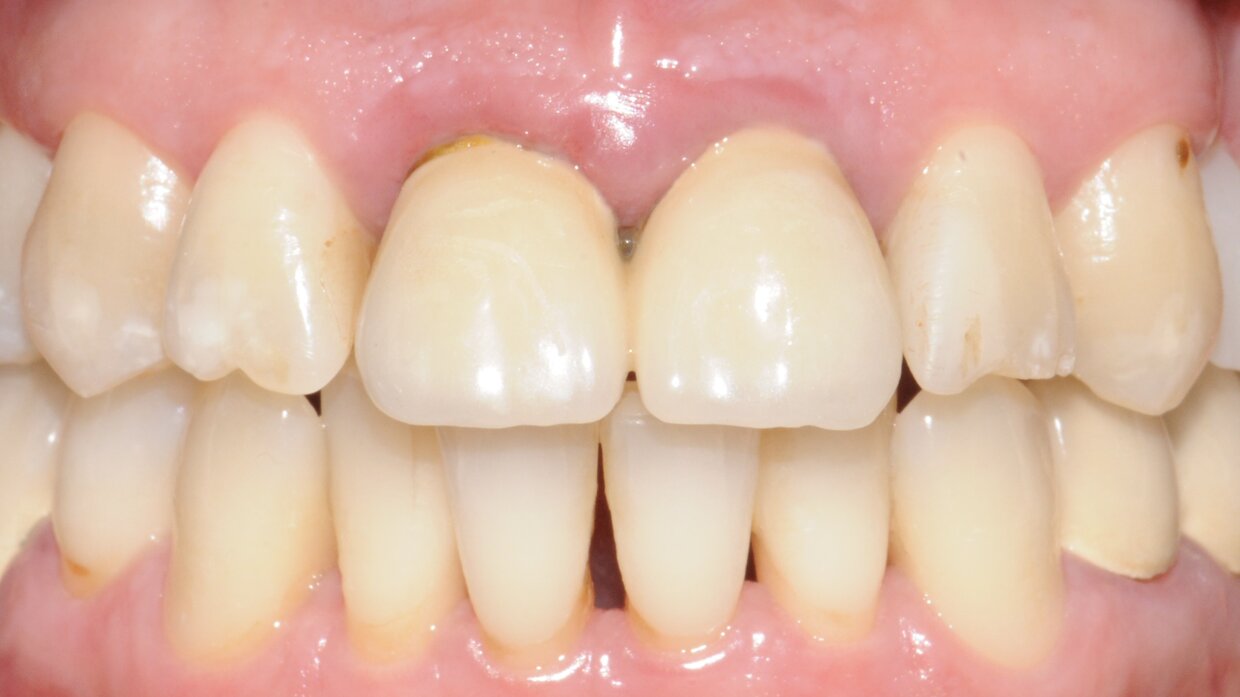

Impianto con tecnica Flapless

Minimamente invasivo, senza lembo chirurgico nè punti di sutura

Il posizionamento degli impianti è stato pianificato prima dell'intervento su un software dedicato. In un'unica seduta, dopo l'estrazione degli elementi dentari compromessi, sono stati immediatamente inseriti gli impianti nella posizione pianificata, grazie alla realizzazione della dima chirurgica. Per ridurre il riassorbimento osseo a lungo termine e garantire quindi una maggiore resa estetica (vista la zona d'intervento), la chirurgia è stata eseguita con una particolare tecnica denominata: Socket Shield Technique.